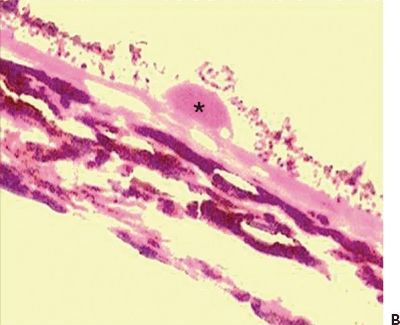

On microscopy, areas of geographic atrophy lack photoreceptors and RPE cells, and the outer plexiform layer is adherent to the BM (Fig. 5.3A and B) (4). This is seen as hypopigmented or atrophic areas overlying a diffusive thickened inner aspect of the BM (26). Calcified or retractile drusen, as previously described, are also observed (28). The RPE demonstrates other changes such as hypertrophy and hyperplasia, which are clinically seen as focal hyperpigmentation (23). Clumps of pigmented cells in the subretinal space and the outer retinal layers may also be observed histologically (26).

Figure 5.3 Geographic atrophy. A. Retinal and choroidal tissue. Photoreceptor lesion with fibrosis (arrow) H&E stain 20×. B. Macular retinal atrophy and fibrosis (arrow). Masson trichrome digital stain 60×. (Courtesy Zárate JO, Alvarado M© 2011. Unpublished data.)